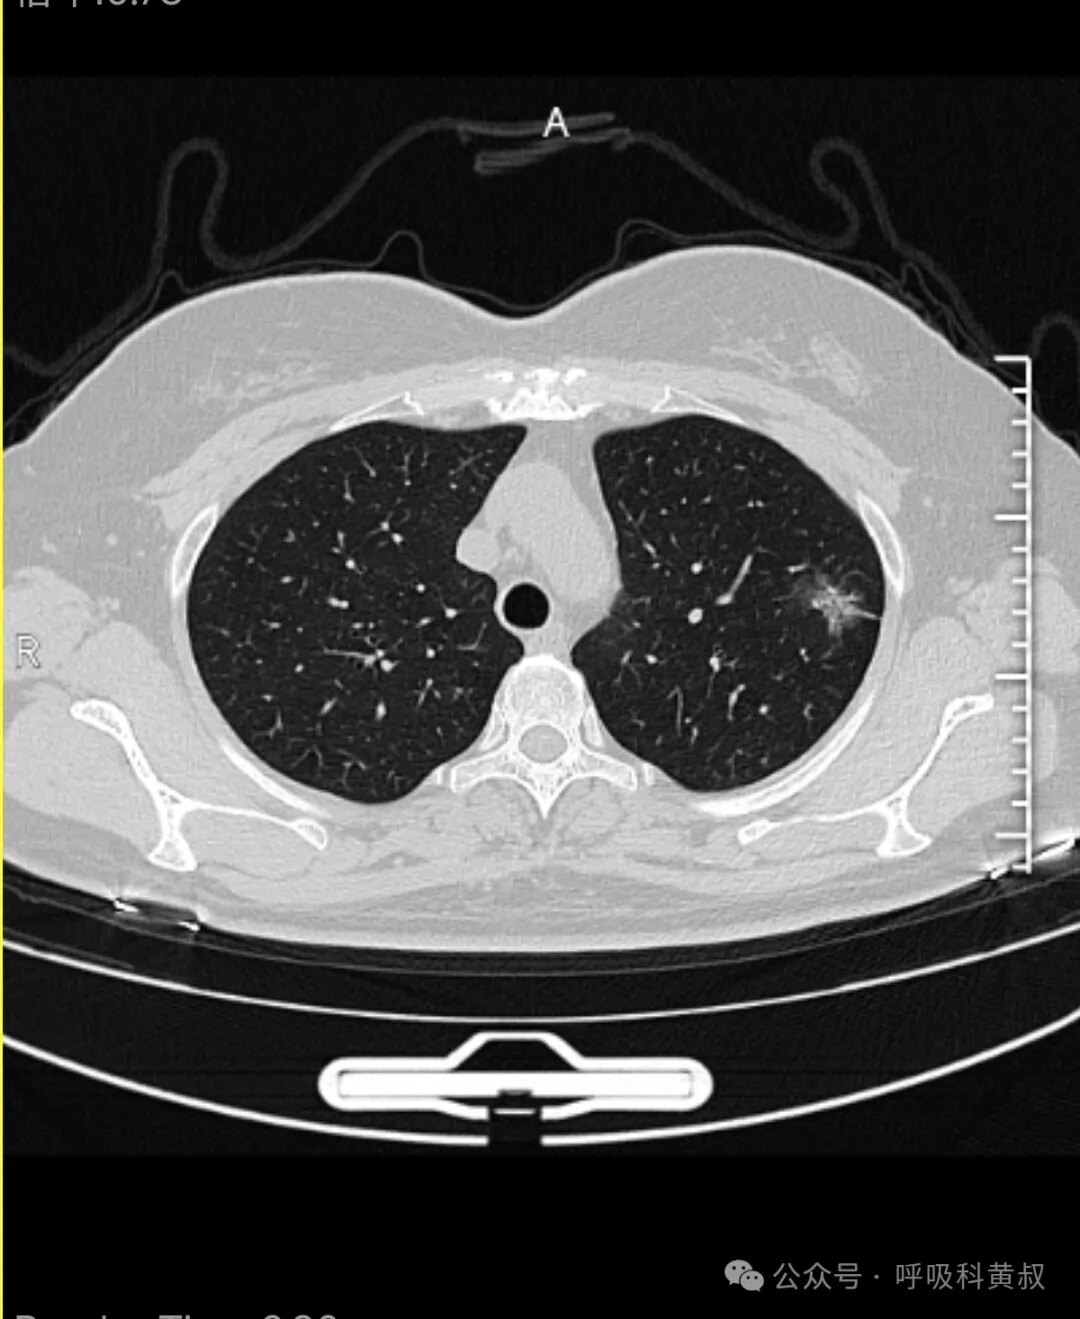

這是一位線上問診的患者,第一次發(fā)現(xiàn)肺部結(jié)節(jié),結(jié)節(jié)位于左肺上葉這個(gè)混合磨玻璃結(jié)節(jié)是一個(gè)典型的惡性結(jié)節(jié),胸膜牽拉,磨玻璃成分邊界很清晰。下面是放大后的影像,惡性表現(xiàn)很明顯??梢院芸隙ǖ暮突颊哒f惡性結(jié)節(jié),建議其手術(shù)。后續(xù)患者馬上進(jìn)行了手術(shù),病理提示惡性。更多病例分享,可關(guān)注公眾號(hào)呼吸科黃叔